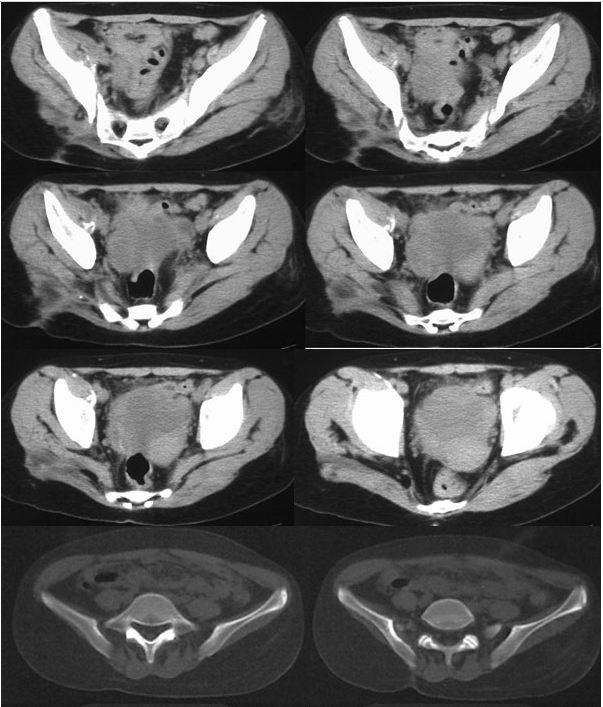

我的好友丹丹,老家有一个表妹,今年16岁,1年前无明显诱因出现右臀部酸痛,伴畏寒、发热、午后低热、盗汗,无双下肢放射痛,并出现左臀部皮肤红肿、破溃、流脓,曾在当地卫生院间断诊治,予以口服药物治疗,效果差,后逐渐出现右臀部外侧皮肤破溃、流脓,经自行口服药物后窦道自行愈合后,周围再次出现流脓,经久不愈,时有脓液流出。丹丹前两天回到老家,把表妹接到我院住院治疗。骨科专科检查发现右臀部一个约0.5x0 5 cm大小窦道口,按压周围可见黄色干酪样分泌物流出,局部可见肉芽组织,无红肿,周围可见多个窦道口疤痕。胸部X线检查:右上.中肺野及左中肺野可见片状.斑片(点)状.条索状阴影,边缘清晰,密度均匀。骨盆CT检查:右侧骶髂关节面骨质破坏、硬化,正常关节结构破坏,臀部软组织内可见囊性密度不均之肿块,影像诊断:右上.中肺.左中肺结核,右侧骶髂关节结核伴髂内肌冷脓肿形成、关节半脱位。

骶髂关节结核常见影像学表现为骨质破坏,死骨形成,关节间隙增宽或变窄,周围脓肿形成,部分伴有窦道。骨盆的X线平片检查可明显的看出骨质的改变,部分脓肿,但由于解剖结构的特殊性,无法显示全部的关节间隙。CT的密度分辨率较高,能够清晰的显示骨破坏程度、部位以及范围,对死骨、脓肿的形成及部位、窦道、囊肿等能够直观的检查,可以发现到X线检查难以观测的生理性骨化和病理性改变。

骶髂关节结核影像学表现:滑膜型结核早期关节囊肿胀,关节间隙增宽,继而侵及关节软骨和关节面;骨型结核早期在骶髂关节的骶骨或髂骨端见到孤立的圆形或椭圆形破坏区,边缘清楚,继而病变累及关节软骨和滑膜,导致关节边缘模糊、毛糙,骶髂关节前下部受累最早,且以髂骨侧破坏最严重。随着病变的进展,滑膜被增生的肉芽组织替代,干酪样坏死物聚集、侵蚀,死骨形成,最终使全关节受累,韧带软化、松弛,关节间隙增宽,这有别于其他大关节。由于骶髂关节结核的骨质疏松常不如其他关节明显,而往往显示有骨质增生硬化征象。关节破坏严重者,可造成病理性半脱位。大多有冷脓肿形成,多发生在臀部,有时在腹股沟、髂窝区,当脓肿增大,张力增高时,常自行破溃并沿着薄弱的组织间隙蔓延形成窦道。

骶髂关节结核典型CT表现:

(1)骨型骶髂关节结核呈圆形或椭圆形破坏区,并累及髂骨侧关节面。

(2)滑膜型骶髂关节结核呈:①关节面模糊、破坏,骨质破坏,关节间隙狭窄或不规则增宽;②大块死骨或散在颗粒状高密度影;③骨质增生硬化。